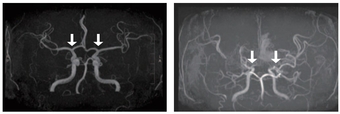

[사진 왼쪽부터] 정상 및 모야모야병 환자의 뇌혈관